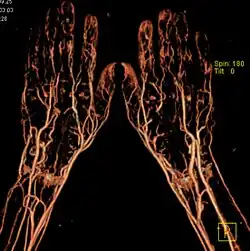

Trójwymiarowa angiografia dopplerowska (ultrasonografia trójwymiarowa)

Analizuje całkowite unaczynienie zmian, pozwala na wprowadzenie ilościowej oceny zarówno unaczynienia, jak i przepływu krwi (możliwe jest to dzięki wprowadzeniu metody kolorowego dopplera). Umożliwia analizę zarejestrowanego obszaru we wszystkich trzech płaszczyznach, umożliwiając tym samym rekonstrukcję przekrojów, których nie można ocenić techniką konwencjonalną. Wykorzystywana zwłaszcza w ocenie guzów jajników, poprawia również wyniki przewidywania wystąpienia zmiany złośliwej. Obecnie metoda ta stanowi cenne uzupełnienie konwencjonalnej diagnostyki USG[5].